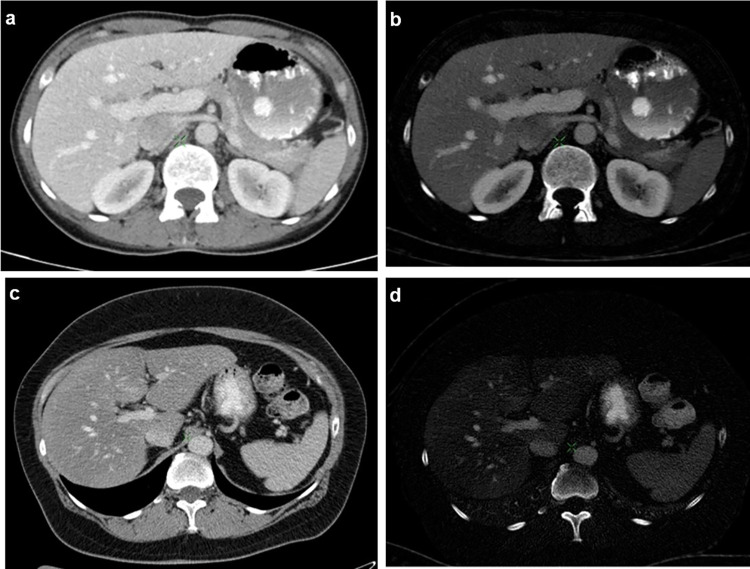

Figure 3 shows an example of the difference between the iodine uptake of healthy and fatty liver parenchyma in quantitative iodine images.

Fig. 3.

Portal venous phase DECT images of the upper abdomen in transverse plane. a, c One hundred twenty-kilovoltage peak HU images. b, d Material density iodine concentration images. The images in the upper row present the liver parenchyma of a 52-year-old male, healthy patient (CT value: 111 HU; iodine value: 2.75 mg/ml). In the lower row, DECT of the liver of a 51-year-old male patient with hepatic steatosis is shown, with lower CT value (68 HU) and decreased iodine value (0.88 mg/ml)